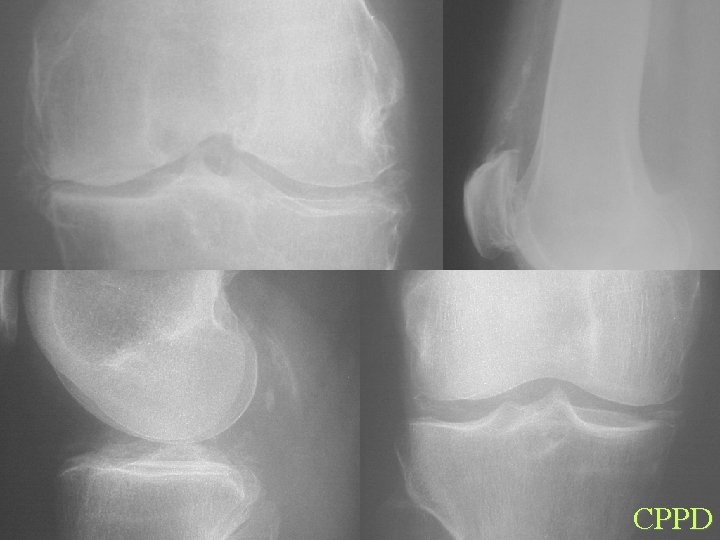

CPPD

Calcification By site Articular cartilage • Osteoarthrosis • • CPPD HADD Hyperparathyroidism Haemochromatosis